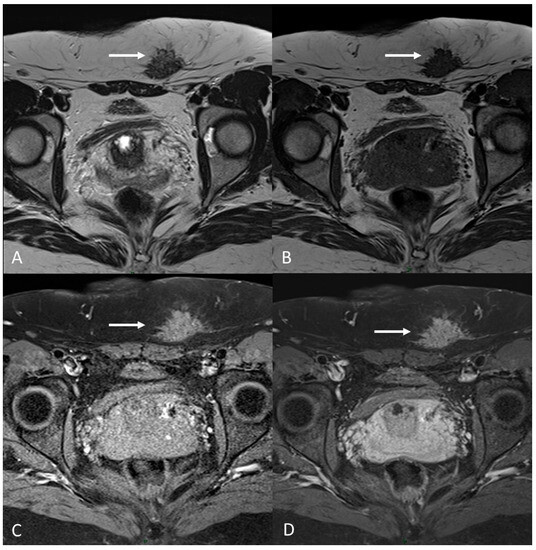

Generally, they appear hyperintense on fat-suppressed T1WI and T1WI (Figure 7 and Figure 8). The hyperintensity on fat-suppressed T1WI helps differentiate endometriomas from dermoid cyst and teratoma, which usually contain fat [51]. On T2WI, a variable signal can be obtained: a hypointense signal can affect variable portions of the cyst, sometimes also presenting a stratification, until a complete loss of the signal. This is called the shading sign and is correlated to the different state of hemoglobin degradation [52] (Figure 8). The T2 dark spot sign refers to hypointense spots in the wall of the cyst due to the presence of macrophages (Figure 9).

Figure 7.

Ovarian endometrioma in a 37-year-old female. (A) Axial T1WI; (B) Axial fat-suppressed T1WI. Typical aspect of an ovarian endometrioma (white arrows).

Figure 8.

Right tubo-ovarian endometriosis in a 25-year-old female patient with reported localized abdominal pain in the right iliac fossa, which increases intensity during the menstrual cycle. (A) Axial T2WI; (B) Axial fat-suppressed T1WI. Enlarged right adnexal cyst with incomplete septa denoting dilated tube (white arrows). The cystic content shows low signal intensity on T2WI and high signal intensity on fat-suppressed T1WI, consistent with hemorrhagic fluid.

Figure 9.

Diffuse internal and external adenomyosis in a 37-year-old female. (A) Sagittal T2WI; (B) Axial T2WI. Diffuse internal adenomyosis as demonstrated by diffuse hypertrophy of the JZ (white arrowhead in (A,B)), subserosal hypointense ill-defined mass in the posterior myometrium consistent with external adenomyosis (white dotted arrows in (A,B)), with associated deep endometriosis of posterior compartment. Left endometrioma with T2 dark spot sign (white arrow in (B)).